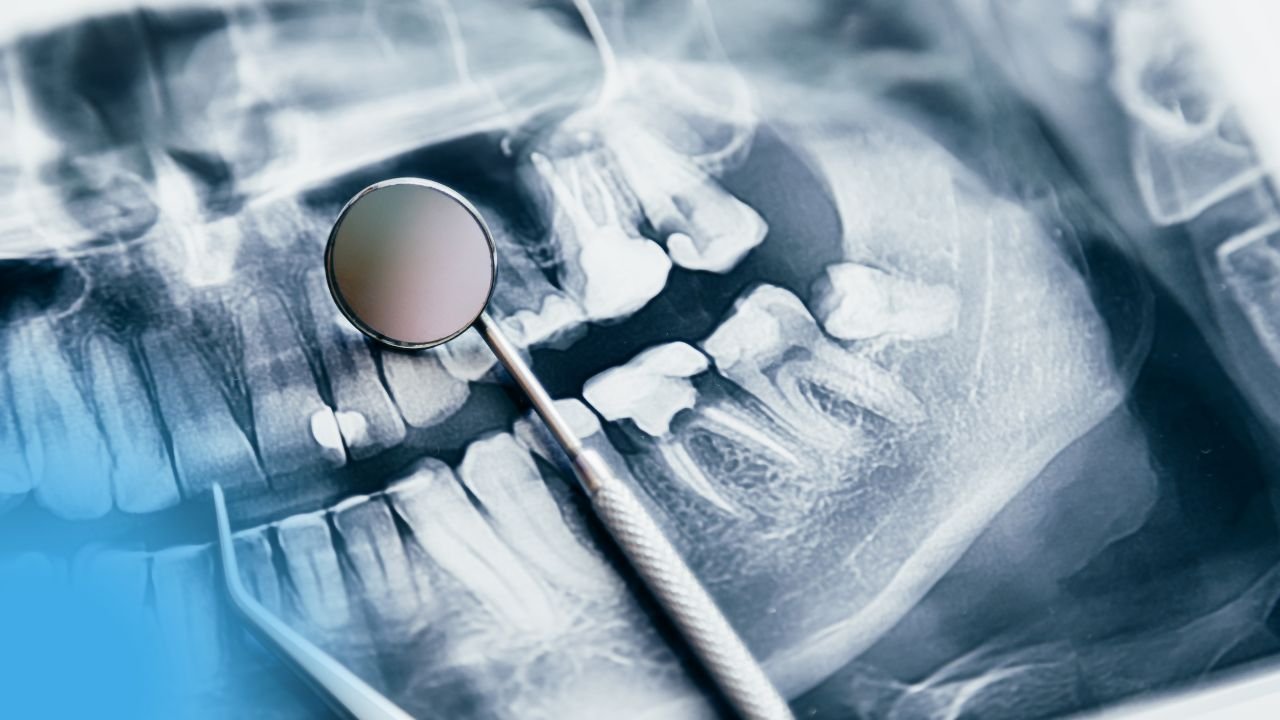

Les Fractures de la Mandibule / Pathologie et chirurgie buccale Généralités Introduction La mandibule est l’un des segments du squelette...

Lire l'articleLes Fractures de la Mandibule / Pathologie et chirurgie buccale Généralités Introduction La mandibule est l’un des segments du squelette...